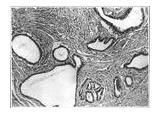

輸卵管結紮術後外側殘留段扭轉,導致出血性梗死查體